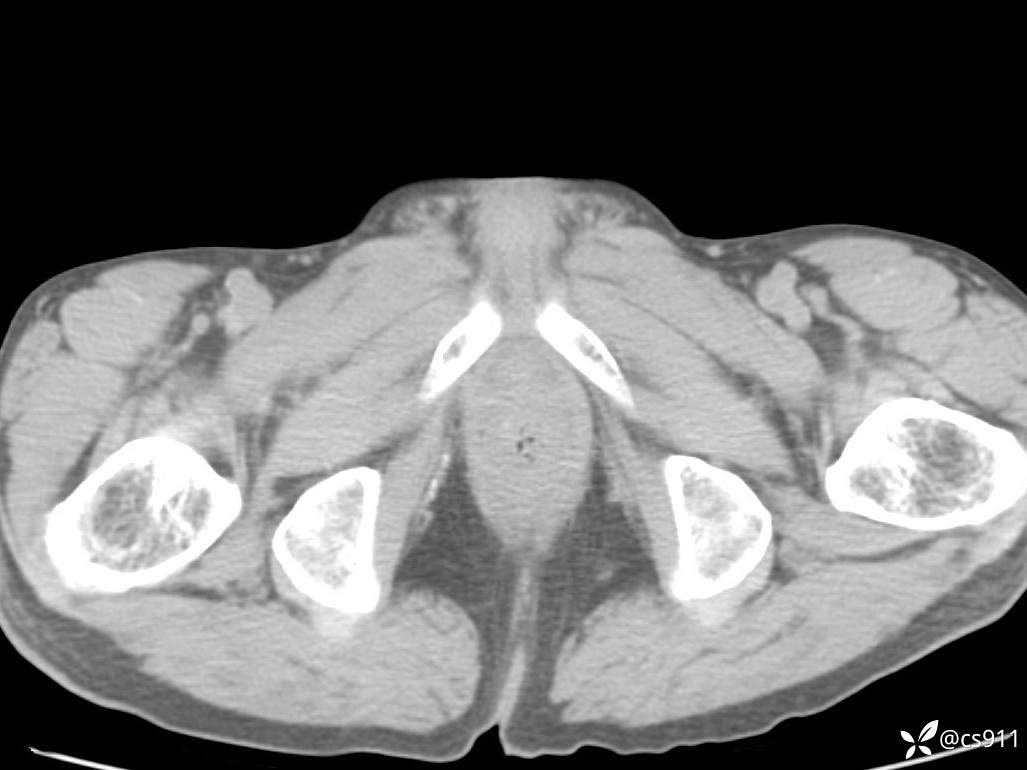

急腹症之急诊CT,原因?答案公布

男,77岁,腹痛、腹胀伴恶心呕吐1天。呕吐胃内容物,非喷射性呕吐,有咖啡色样胃内容物,诉有胃穿孔病史。查体:全腹平,下腹部压痛,全腹无反跳痛,叩诊呈浊音,移动性浊音阴性,肠鸣音减弱,1-2次/分。肛检:直肠未扪及明显肿物,可触及大量粪块。

血淀粉酶(AMY) HH 1859 U/L 35-135